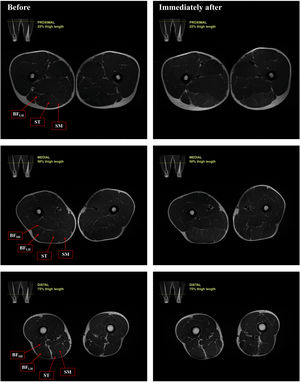

ResultsRepresentative T2-weighted magnetic resonance images before and immediately after the 10 × 10 FRD training session are presented in Fig. 3. A significant main effect for time were observed for the T2 values [F(1106) = 51,838.462, p < 0.001]. T2 values substantially increased from the basal condition to immediately after exercise in all regions of all the hamstring muscles in both dominant and non-dominant lower limb (Table 1).

Representative T2-weighted magnetic resonance images of the proximal region (25 % of thigh length), middle region (50 % of thigh length) and distal region (75 % of the tight length) before and immediately after the Flywheel Russian belt deadlift training session. BFSH, m. biceps femoris short head; BFLH, m. biceps femoris long head; ST, m. semitendinosus; SM, m. semimembranosus.

Selected magnetic resonance images acquired before and immediately after the Flywheel Russian belt deadlift training session, depicting regions of interest (ROIs). 1, m. biceps femoris short head (BFSH); 2, m. biceps femoris long head (BFLH); 3, m. semitendinosus (ST); 4, m. semimembranosus (SM).